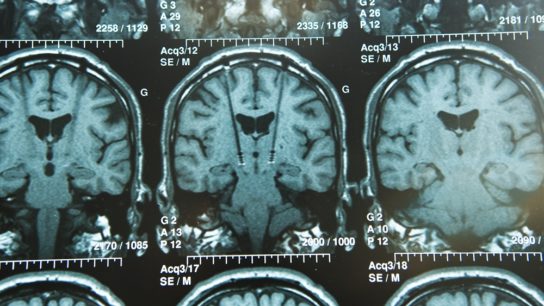

MRI may be used to identify Parkinson disease biomarkers that can inform diagnosis, track disease progression, and elucidate the neurobiological underpinnings of symptoms.